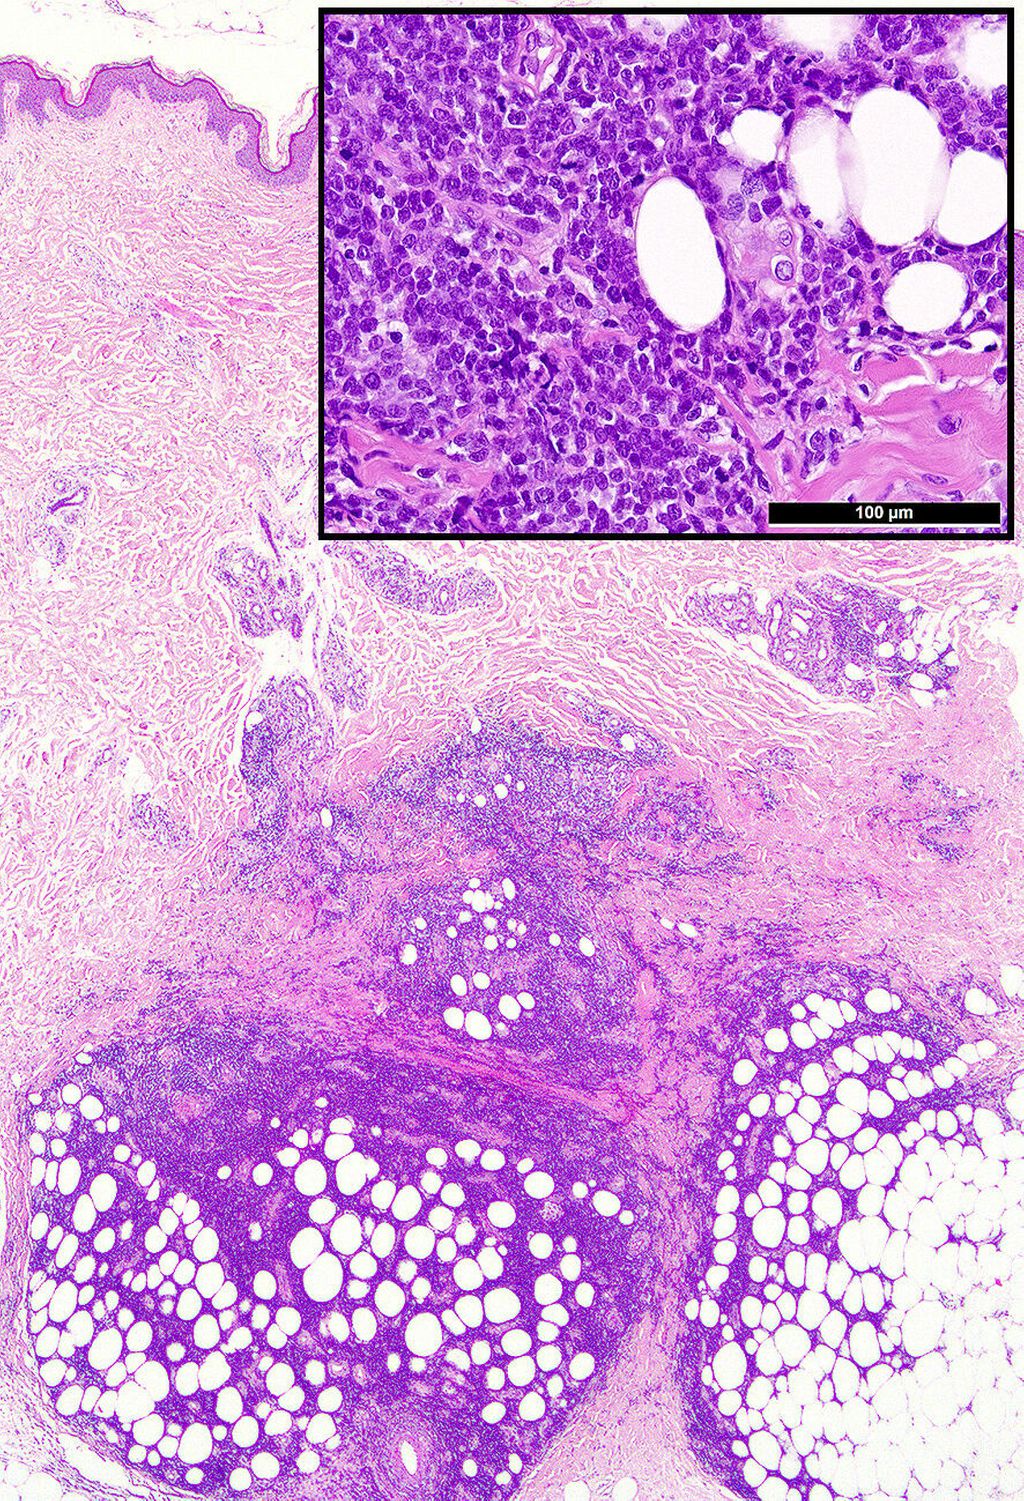

Abb. 1: Typische Präsentation einer Leukaemia cutis mit tiefenbetontem periadnexalem dermalem und interstitiellem bis kleinnodulärem subkutanem unreifzelligem (Einsatz-)Infiltrat

Die histologische Diagnose ist bei einer bekannten oder simultanen Leukämie einfach. Die meisten LC präsentieren sich als unreife klein-, blau- und rundzellige Tumoren (KBRZT) mit einer tiefer als erwarteten interstitiellen, perivaskulären, periadnexalen oder nodulären Infiltration der Dermis bzw. der Subkutis unter Aussparung der oberen Dermis (Grenzzone; Abb. 1); ALL betrifft in der Regel tiefere Strukturen.